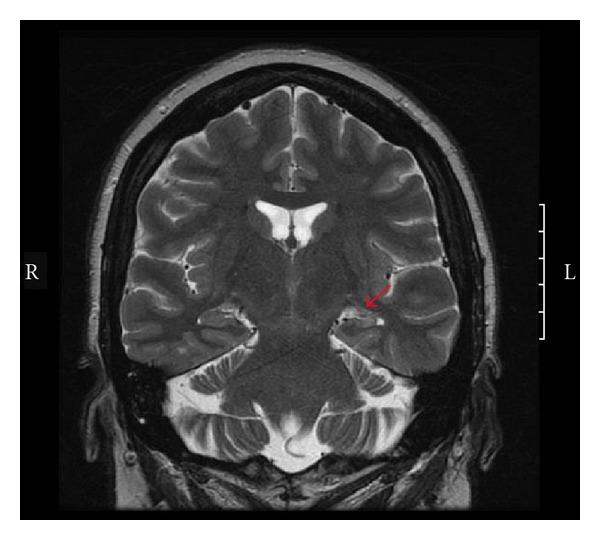

Treatment of epilepsy often imposes an exposure to various antiepileptic drugs and requires long-term commitment and compliance from the patient. Although many new medications are now available for the treatment of epilepsy, approximately 30% of epilepsy patients still experience recurrent seizures and many experience undesirable side effects. Treatment of epilepsy requires a multidisciplinary approach. For those patients with medically refractory seizures, surgical treatment has increased in prevalence as techniques and devices improve. With increased utilization, proper patient selection has become crucial in evaluating appropriateness of surgical intervention. Epilepsy syndromes in which surgery has shown to be effective include mesial temporal sclerosis, cortical dysplasia, many pediatric epilepsy syndromes, and vascular malformations. Monitoring in an epilepsy monitoring unit with continuous scalp or intracranial EEG is an important step in localization of seizure focus. MRI is the standard imaging technique for evaluation of anatomy. However, other imaging studies including SPECT and PET have become more widespread, often offering increased diagnostic value in select situations. In addition, as an alternative or adjunct to surgical resection, implantable devices such as vagus nerve stimulators, deep brain stimulators, and direct brain stimulators could be useful in seizure treatment.

癫痫的治疗通常需要使用各种抗癫痫药物,并且要求患者长期坚持并遵守治疗方案。尽管现在有许多新药物可用于治疗癫痫,但仍有大约30%的癫痫患者会经历癫痫复发,而且许多患者会出现不良副作用。癫痫的治疗需要多学科方法。对于那些药物难治性癫痫发作的患者,随着技术和设备的改进,手术治疗的普及率有所提高。随着手术治疗的使用增加,在评估手术干预的适用性时,正确选择患者变得至关重要。手术已证明有效的癫痫综合征包括内侧颞叶硬化、皮质发育异常、许多小儿癫痫综合征以及血管畸形。在癫痫监测单元中通过持续头皮或颅内脑电图进行监测是确定癫痫发作灶位置的重要步骤。MRI是评估解剖结构的标准成像技术。然而,包括SPECT和PET在内的其他成像研究已变得更加普遍,在某些情况下通常能提供更高的诊断价值。此外,作为手术切除的替代或辅助方法,迷走神经刺激器、深部脑刺激器和直接脑刺激器等可植入设备在癫痫治疗中可能会发挥作用。